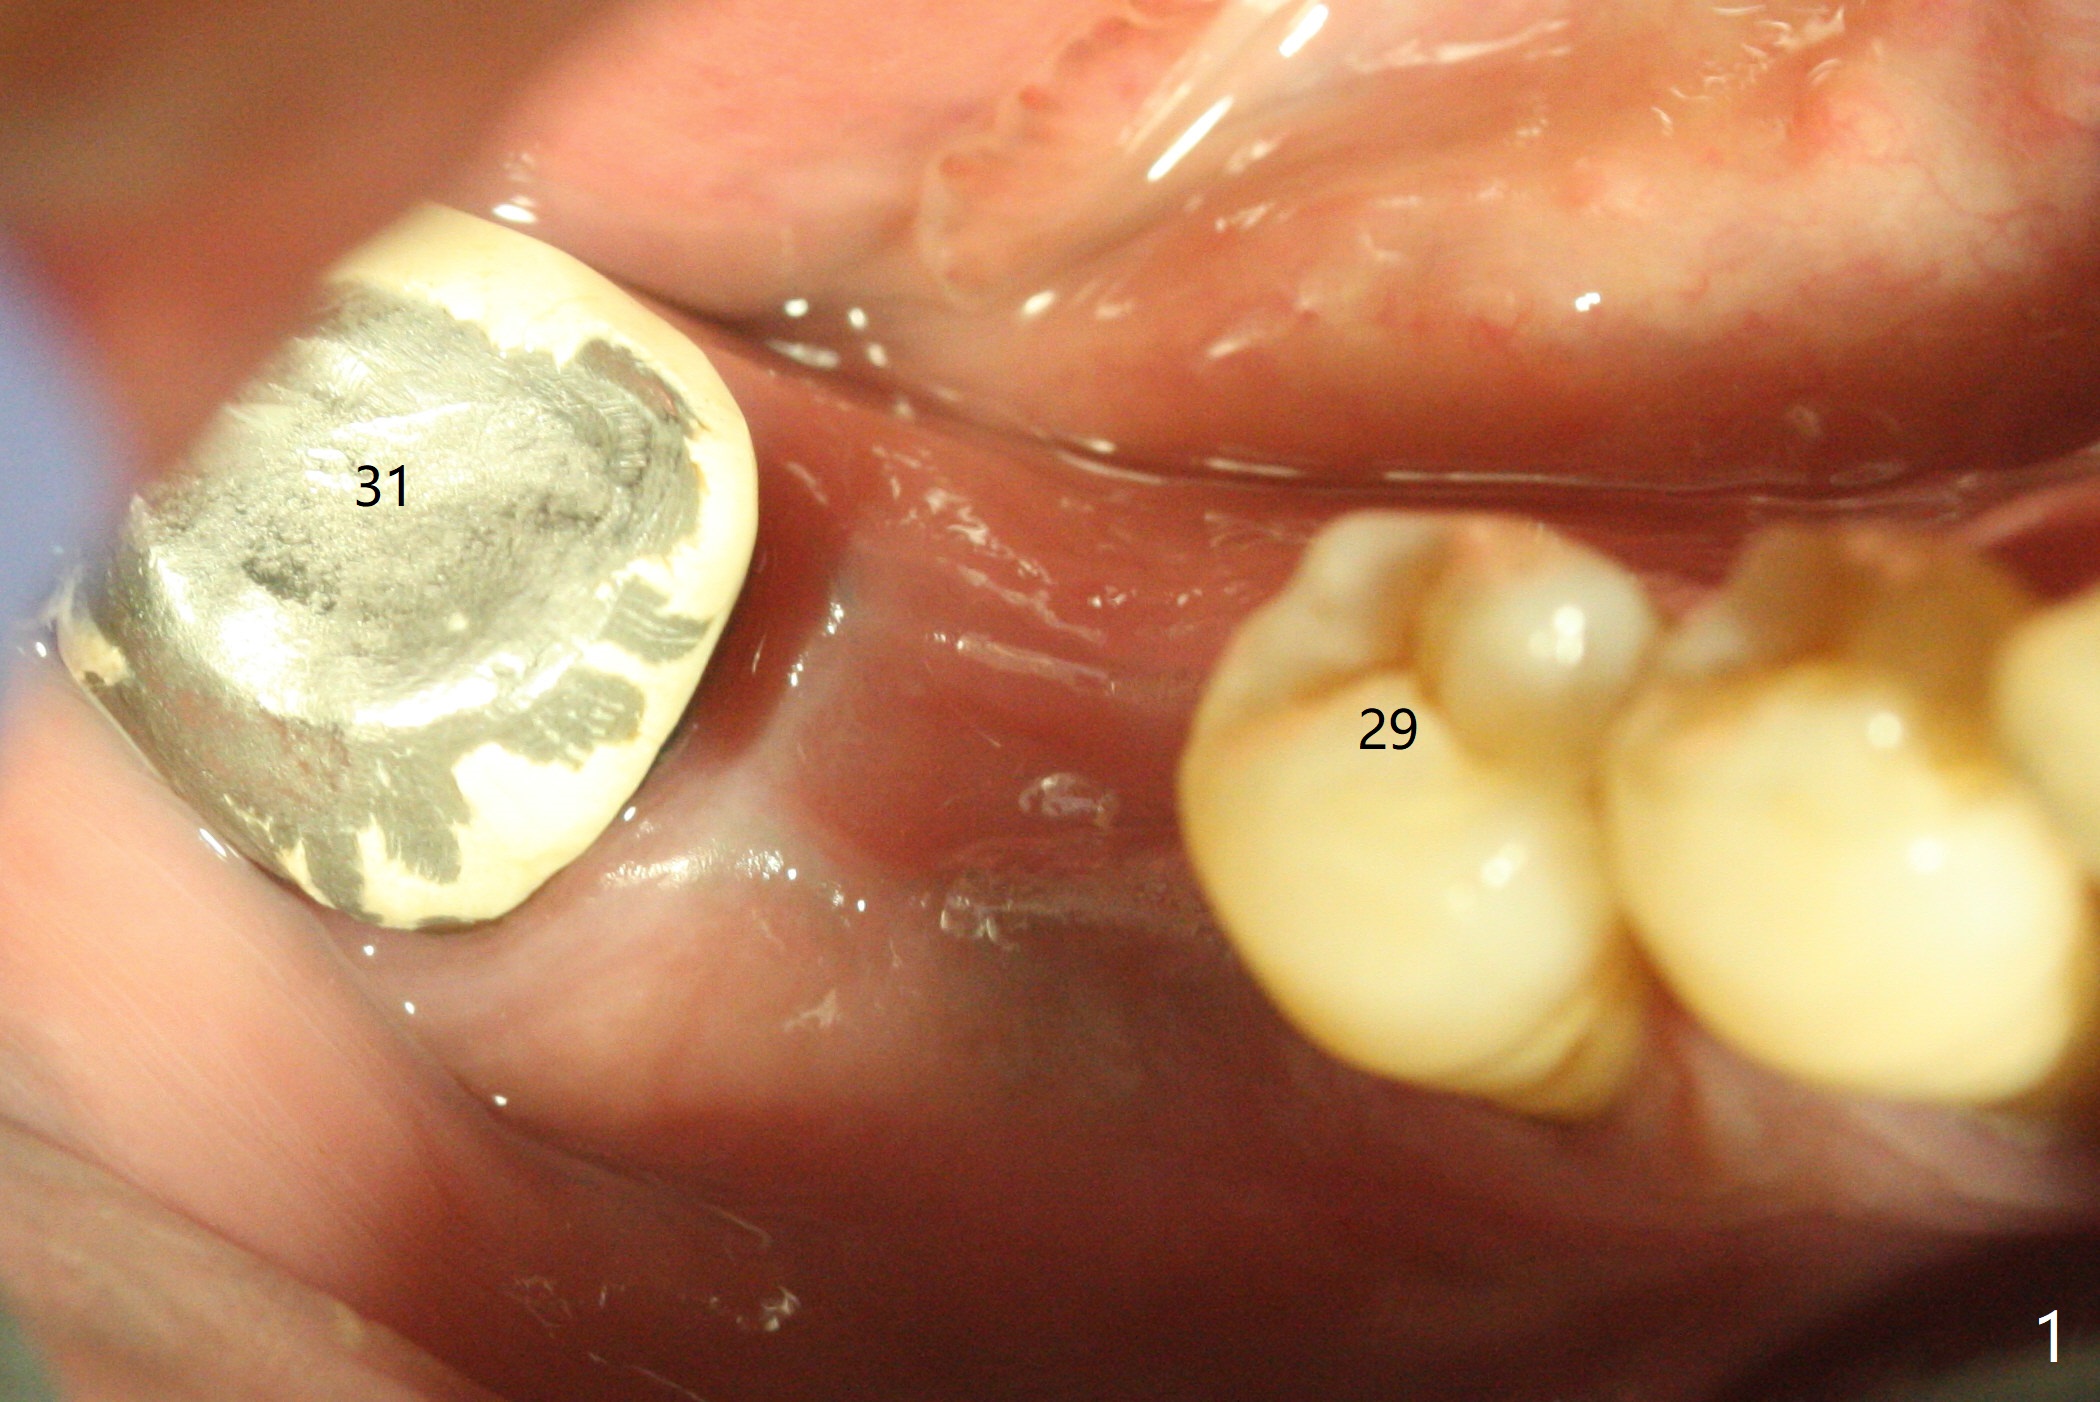

The sockets of #30 (M) of a smoker (M) are apparently not healing ~ 2 months post extraction (Fig.0, 0'). The ridge looks wide 3 months post extraction without bone graft in other office before (Fig.1) and after (Fig.2) flap surgery. The socket appears to have healed perfectly consi-dering buccal defect (M) revealed by CT ~ 1 month earlier. When a 5x10 mm implant is placed with guide and high torque (in spite of overprep), granu-lation tissue is found mesio-buccal (MB, Fig.2 *). After curettage, bone graft is placed around the implant, especially MB (Fig.3 *), followed by PRF. Periodontal dressing dislodged a few days postop because of mastication on the right side (Fig.4), whereas the anterior one (24/26) remains in place. There is a small gap around the implant when it is uncovered (Fig.5 arrowheads). It appears that some of bone graft gets lost from the incision (smoker). A 6.5x5.5(4) mm cemented abutment is seated and torqued at 30 Ncm before impression (Fig.6). There is no bone loss 11 months post cementation (Fig.7).